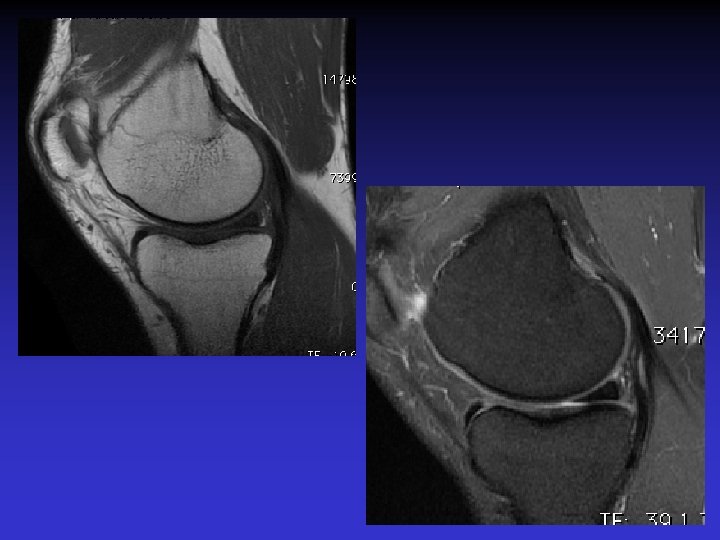

• Homme de 46 ans • Douleurs et sensation de blocage du genou • Pas de traumatisme récent mais « entorse ancienne » • Recherche de lésion méniscale

• • • Pas d’épanchement Pas de lésion méniscale Pas de lésion cartilagineuse Pas de lésion osseuse Anomalies du LCA • Épaissi • Hyper signal T 1 et T 2 • Orientation des fibres conservée • Kyste

ASPECT IRM • • Hyposignal TI Hypersignal T 2 Pas de prise du contraste après Gado IV Continuité conservée du LCA+++ avec dilacération des fibres • Aspect en « tige de céleri »

ASSOCIATION A DES KYSTES MUCOIDES • Dans près de 50% des cas • Au contact ou à distance du LCA